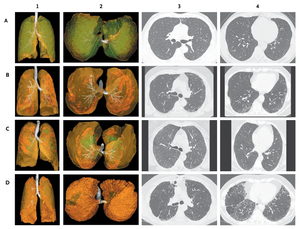

Publication: J Thorac Imaging. 2016 Jan;31(1):29-36. PMID: 26429588| PDF Authors: Zach JA, Williams A, Jou SS, Yagihashi K, Everett D, Hokanson JE, Stinson D, Lynch DA, COPDGene Investigators. Institution: Divisions of Radiology, Biostatistics and Bioinformatics, National Jewish Health, Denver, CO, USA. Background/Purpose: The purposes of this study were to evaluate the effect of smoking status on quantitative computed tomography CT measures of low-attenuation areas (LAAs) on inspiratory and expiratory CT and to provide a method of adjusting for this effect. Materials and Methods: A total of 6762 current and former smokers underwent spirometry and volumetric inspiratory and expiratory CT. Quantitative CT analysis was completed using open-source 3D Slicer software. Funding:

Examples of CN on CT. Coronal CT image of a GOLD 1 subject with moderately extensive visual extent of emphysema. However, the quantitative emphysema score was only 5.1%. The emphysema may have been masked on quantitative assessment by the presence of centrilobular nodules (circled) and patchy ground-glass abnormality (arrows). |